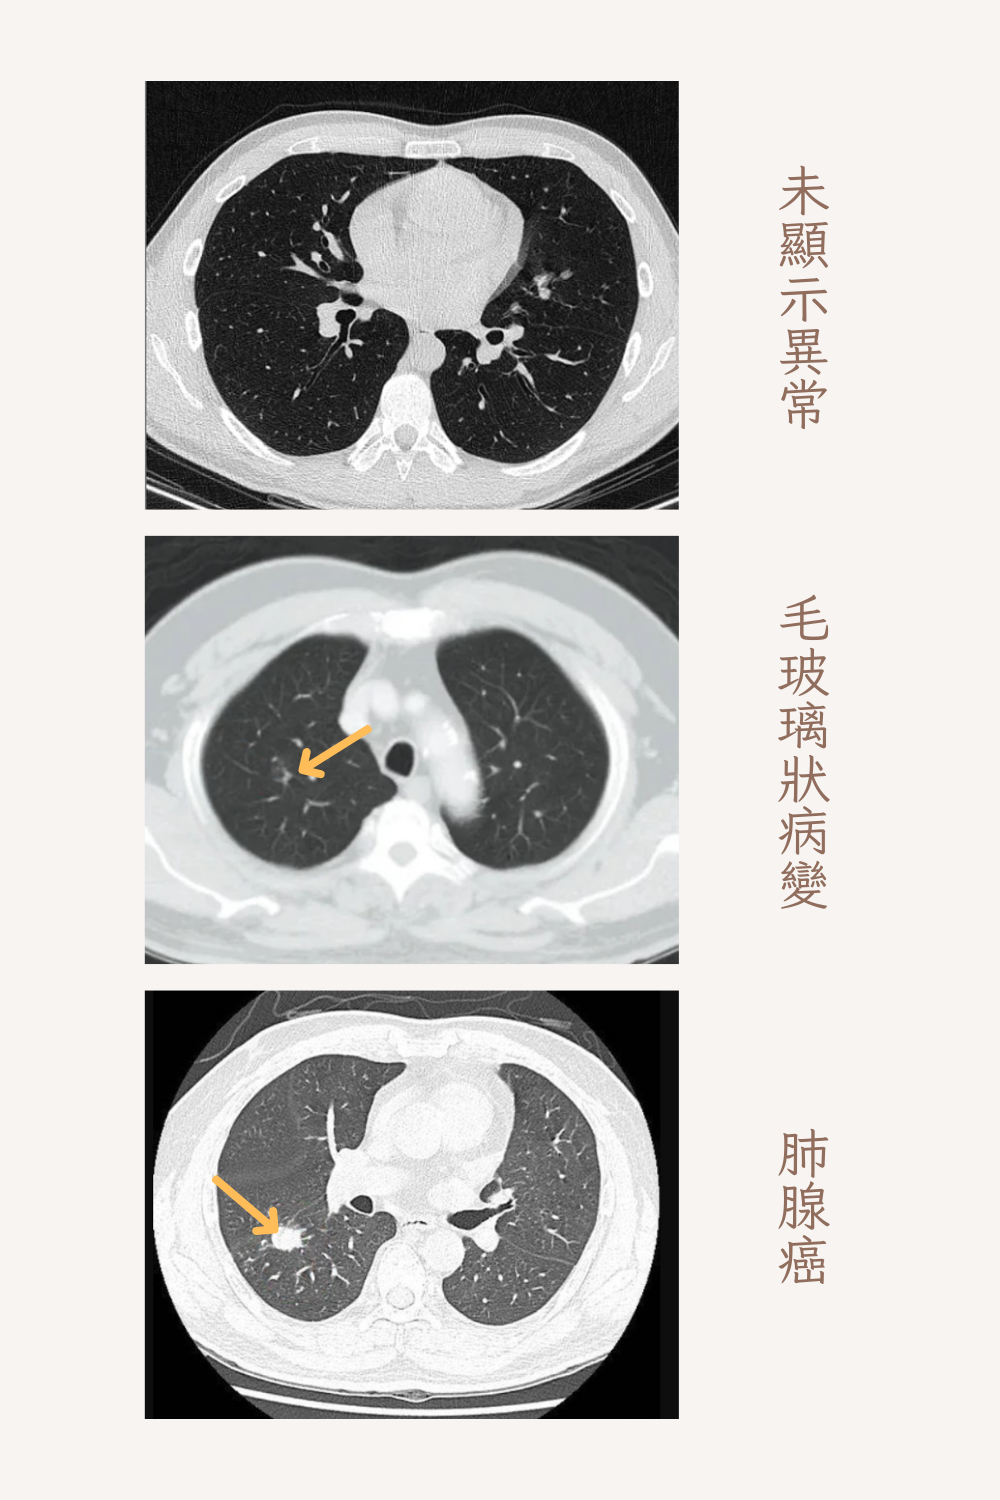

低劑量電腦斷層(LDCT) 是目前公認最有效的早期肺癌篩檢工具。最大特色在於輻射劑量僅為傳統肺部電腦斷層的五分之一,適合用於肺癌篩檢。輻射劑量低、無需使用顯影劑、無痛、非侵入性、檢查快速,檢查時間不到1 5分鐘,安全性更高。檢查主要包含

肺部微小結節的檢測

早期發現微小結節、提高早期診斷率、其他肺部病變的檢測

除了肺癌,還可檢測其他肺部病變,如肺結核、肺部良性結節或纖維化等。